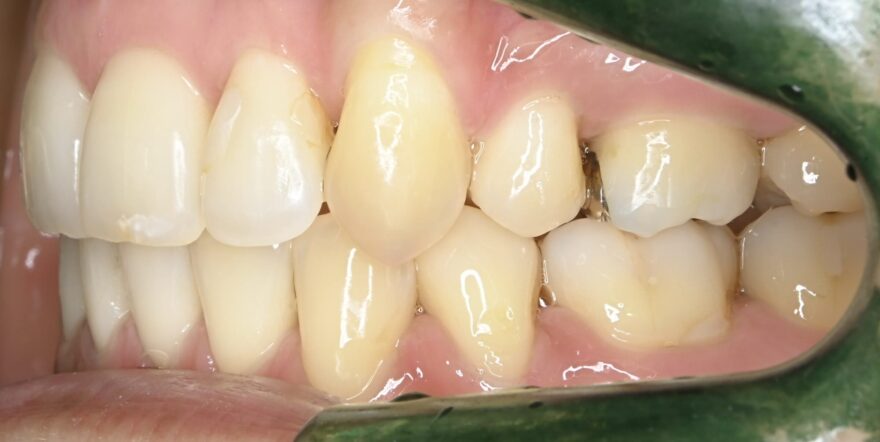

初診時の口腔内写真

同じように、2番目の前歯が、内側に引っ込んでいます。

前歯のガタガタが無くなりました。